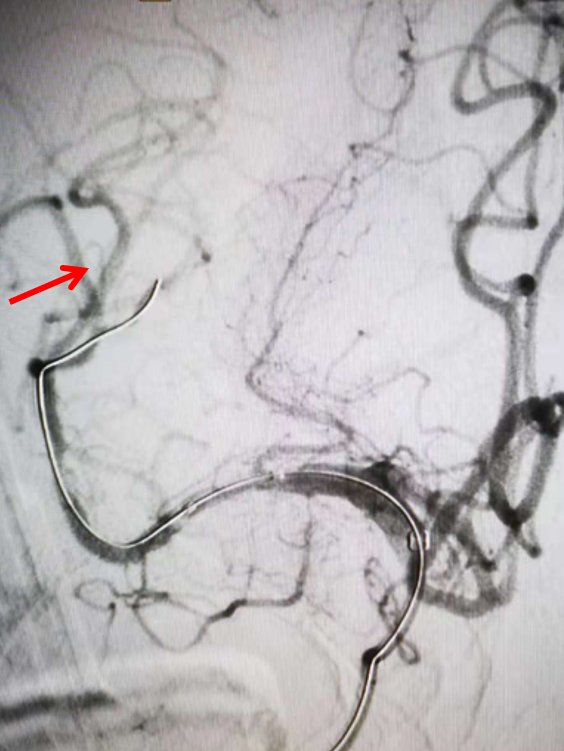

右侧颈总动脉侧位造影:右侧大脑中动脉M2上干、下干均闭塞(箭头示)。

左侧颈总动脉正位造影:双侧大脑前动脉显影,且右侧大脑前动脉通过软膜吻合向右侧大脑中动脉支配区域供血(箭头示)。

左侧椎动脉正位造影:可见双侧大脑后动脉显影良好,且右侧大脑后动脉通过软膜吻合向右侧大脑中动脉支配区域供血(箭头示)。

再次造影证实右侧大脑中动脉上干、下干均闭塞(箭头示)。